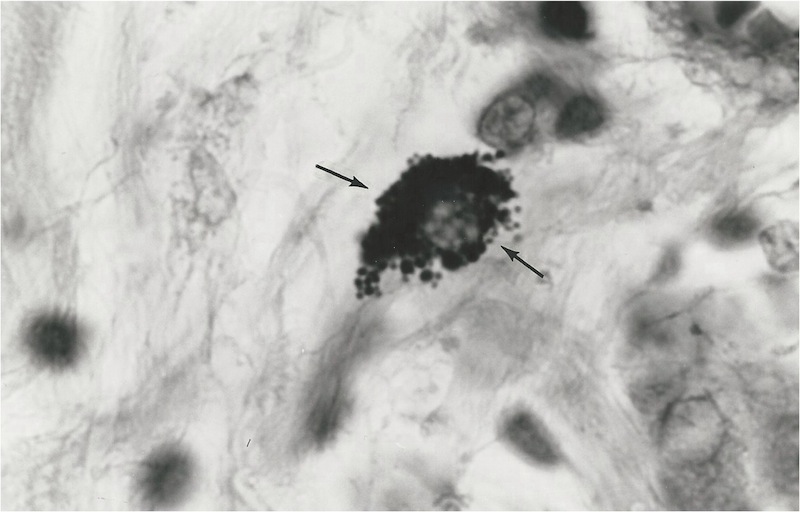

Figure

2. Tissue section of breast cancer showing a nest of extracellular variably-sized

coccoid forms. A collection of red blood cells is seen in the upper

right. Intensified Kinyoun stain, x 1000, in oil.